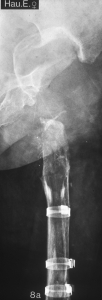

Abb. 12a

SLR-Revisionsschaft

SL-PLUS® Standard Schaft (links) sowie

SLR-Revisionsschaft (rechts)